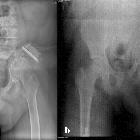

Plain radiograph and CT

- intramedullary or subcortical lucent foci may be the earliest manifestation

- this progresses to profound osteolysis with resorption of affected bone and lack of compensatory osteoblastic activity or periosteal reaction